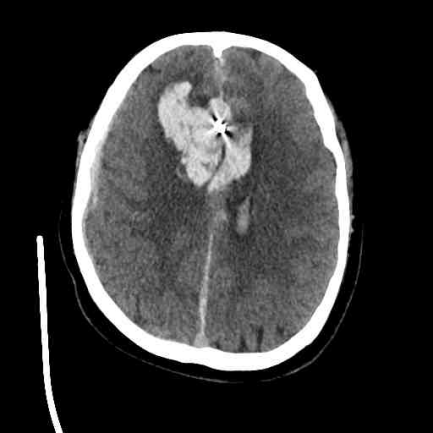

提到脑动脉瘤,很多人以为做完开颅夹闭或介入栓塞手术就万事大吉。但据临床研究:两类手术均存在复发可能!动脉瘤复发率与动脉瘤大小、位置、形态、性质、瘤颈情况、治疗方式、术后即刻结果、抗血小板使用情况等因素相关。因此,定期复查对评估手术效果、术后复发风险及是否需及时干预等至关重要。 真实案例:曾某,54岁,因颅内动脉瘤破裂开颅动脉瘤夹闭术,术后第 3 年突然头痛难忍,复查发现动脉瘤复发并出血,再次行开颅手术挽救了生命。幸亏及时干预才避免悲剧,但不是每个患者都那么幸运! 第一次术前头颅CT 第二次术前头颅CT 划重点:术后定期复查不是“选择题”,而是保命必答题! 为什么要复查? 三大核心目标揭秘 1.评估手术效果:确认动脉瘤愈合情况,是否存在残留或复发。 2.监测并发症:如是否存在脑积水、脑血管狭窄、脑梗死等。 3.调整治疗方案:根据复查结果决定是否需要调整用药或进一步干预。 三大复查项目 1.CT血管成像(CTA):具有快速、经济、无创的特点,可作为颅内动脉瘤术后的常规影像学随访手段,需要静脉注射造影剂后行CT检查,可以较好地显示动脉瘤术后的血管结构,了解动脉瘤夹或栓塞材料的位置及周围血管情况,同时可以显示有无脑积水等情况。 2.磁共振血管成像(MRA):是一种无创检查,不需要注射造影剂,对人体无辐射,能较好地显示脑血管的大致形态和脑动脉瘤术后情况。 3.脑血管造影(DSA):是一种微创检查,为脑动脉瘤检查的“金标准”,它能清晰显示动脉瘤夹闭或栓塞后的情况,准确判断动脉瘤有无残留、复发以及血管的通畅程度。 动脉瘤治疗后复查周期怎么定? 1.对于复发低风险患者:推荐术后1月复查头颅CT,半年和一年连续两次头颅CTA或DSA(至少一次DSA),如两次结果均为治愈,可3-5年复查一次。 2.对于复发风险高的患者:术后3个月、6个月和1年分别进行一次CTA或DSA(至少一次DSA),部分复发风险高的患者甚至在出院前需复查一次CTA或DSA。 3.对于术后动脉瘤夹闭或栓塞效果满意的患者:建议在术后半年或1年完成一次DSA。若复查显示动脉瘤完全闭塞且无显影,后续可延长复查间隔至每3-5年一次。 (以上复查时间仅供参考,具体时间需专科医师个体化决定,详情请咨询神经外科:0830-5216264 ,地址:门诊综合楼二楼204室) 脑动脉瘤复发了怎么办?这些救命知识要知道 如果复查发现动脉瘤复发,千万别慌!虽然复发动脉瘤发生瘤体增大、破裂出血的风险更高,但目前有多种成熟治疗手段。以下是复发动脉瘤处理措施包括但不限于: 1.减少抗血小板药物的使用; 2.再次开颅夹闭术或介入栓塞术或开颅夹闭+介入栓塞复合手术; 3.搭桥或载瘤动脉闭塞孤立动脉瘤术。 随着手术技术及手术材料的发展,动脉瘤复发率正逐年减低,随访周期及方法也在不断地变化,正确、规律的随访仍然是降低动脉瘤致死和致残率的有效方式。 最后敲黑板!三条“生存法则”请牢记 1.术后第一年是复发高峰,务必严格按医嘱复查。 2.出现突发头痛、呕吐、意识模糊等症状,立即就医! 3.选择同时具备开颅 + 介入技术的医院,为二次治疗留足空间 转发提醒:脑动脉瘤被称为“颅内不定时炸弹”,转发本文给身边有需要的人,一次提醒可能挽救一条生命!